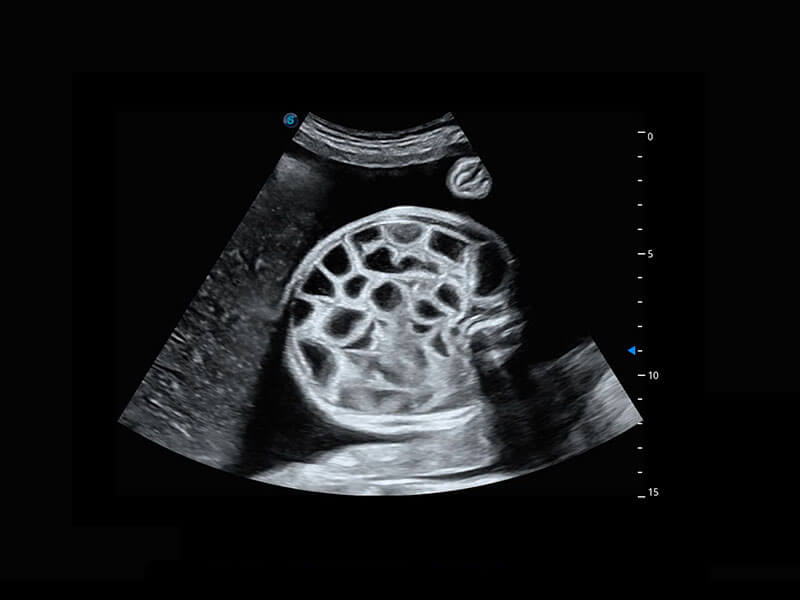

胎心筛查

P60搭载一系列胎儿心脏成像技术,实现精细的胎儿心脏评估。

• 四腔切面

• 四腔心血流

• 胎心容积成像